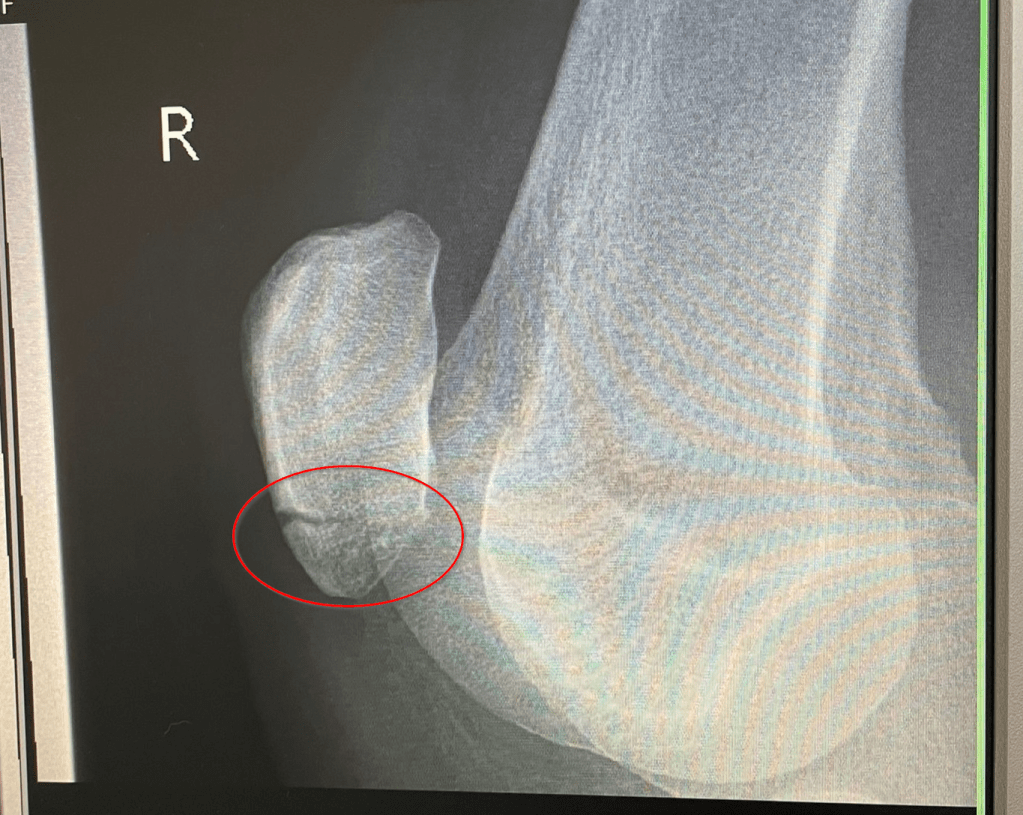

Diese Woche Freitag steht der heiß ersehnte Termin beim Orthopäden an. Das (hoffentlich) letzte Mal röntgen. Wenn ich dort das Okay bekomme, kann es endlich wieder mit dem Laufen und dem Muskelaufbau des rechten Beins los gehen. Momentan ist der Oberschenkelmuskel noch immer eher ein schwabbeliges Etwas und ich freue mich schon darauf, diesen in das zu verwandeln, was er einmal war. Ich bin sehr gespannt, wie der Einstieg ins Laufen klappen wird und wie schnell ich meine Ausdauer wiederaufbauen kann. Ihr werdet es hier auf jeden Fall erfahren!